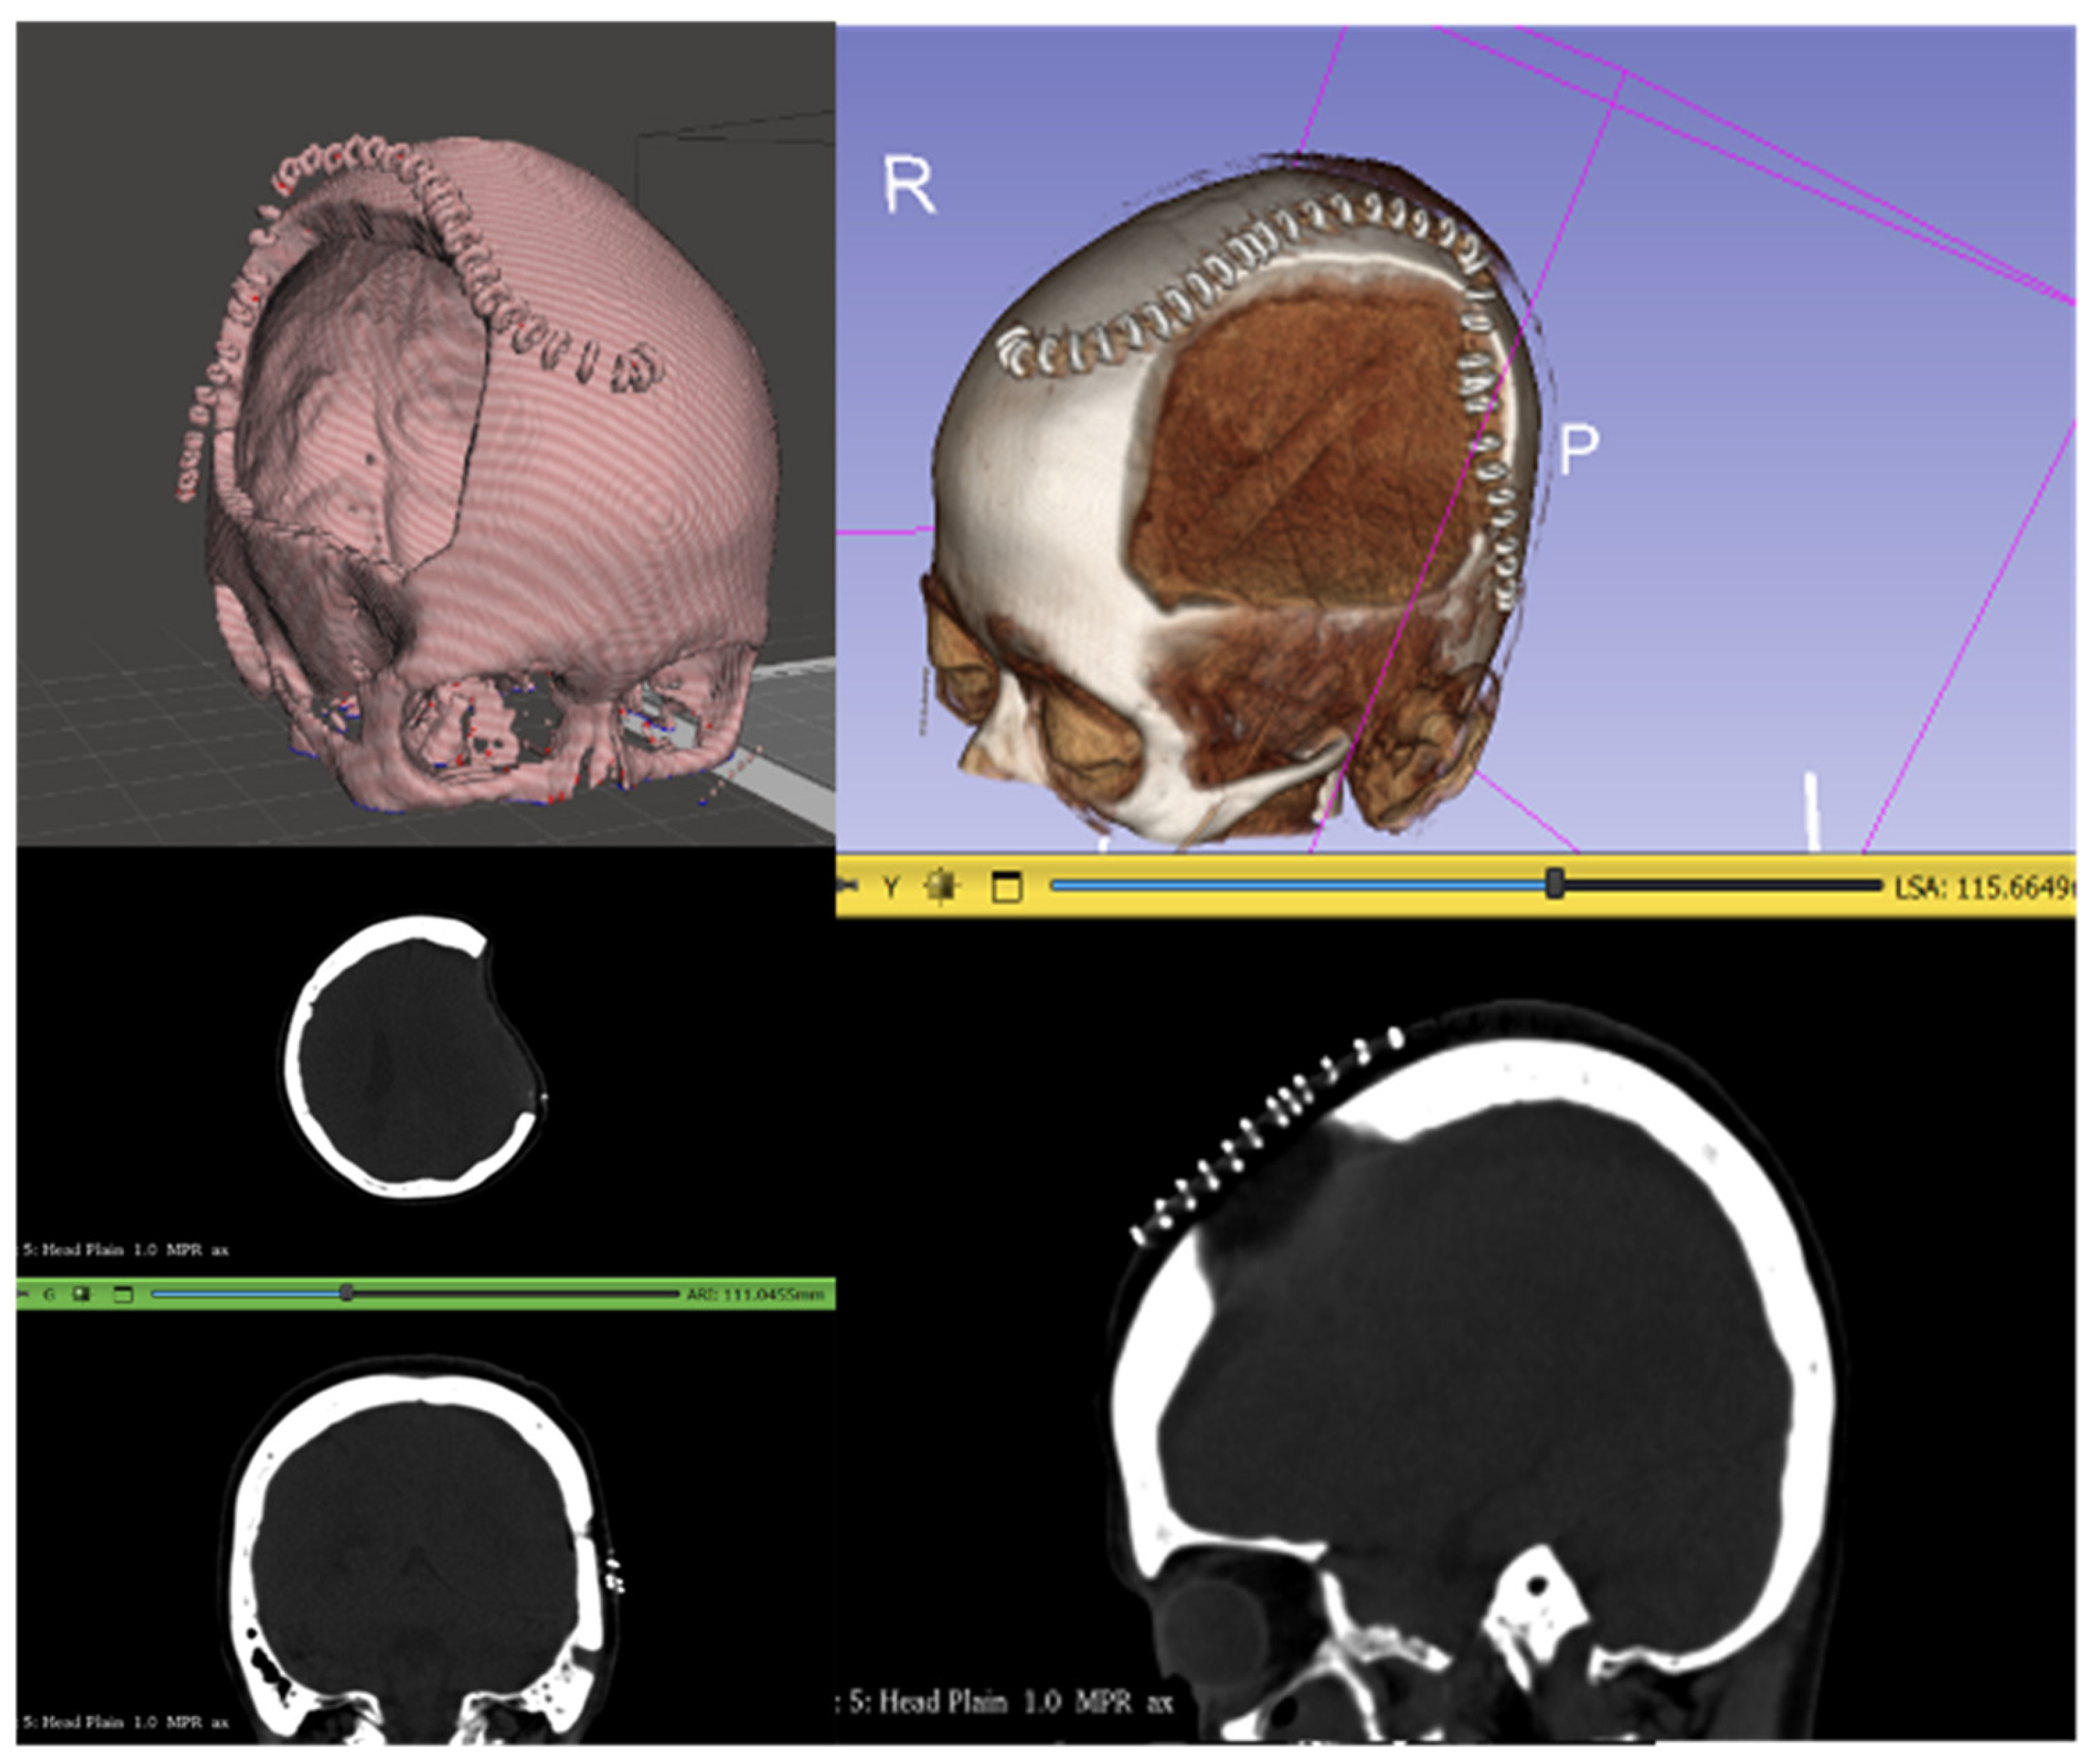

2. Materials and Methods

3. Results

3.1. Feedback from the Philippine Team

| Misidentification of surgical staples as bone. | Some CT scans included surgical staples overlying the DHC and were detected by CranialRebuild as bone, which impacted the software’s determination of the midsagittal plane. | The recommendation was made to acquire CT scans after staple removal (typically 2 weeks after DHC) but before cranioplasty (2–3 months after DHC). | This specific timing of the CT scan should be recommended in the future use of CranialRebuild 2.0. |